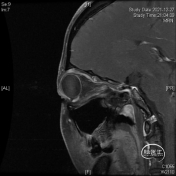

头颅MR体检偶然发现左侧眶尖占位,初步诊断海绵状血管瘤,查体无明显阳性体征。

该部位的手术可选多种入路,经眉弓锁孔、经额、经眶外侧壁等,然而施炜、陈建内镜团队选择了临床较少使用的经眶入路!创伤小且对患者的容貌影响小,术前团队进行了相关解剖研究!

研究表明此入路除细小的滋养血管外无其他重要结构!皮肤切口选择近眶缘眉弓美容切口,紧贴眶上壁分离骨膜,保护眶筋膜,病变紧贴眶上壁,导航下确定眶尖紧贴眶上壁的病变,外观呈浅紫兰色,考虑既往有出血所致,显露肿瘤!

磨除局部少许隆起的骨嵴以增加操作空间,切开眶骨膜分离并完整切除病变,术中证实为海绵状血管瘤,直径约1厘米,手术全程在内镜下完成。